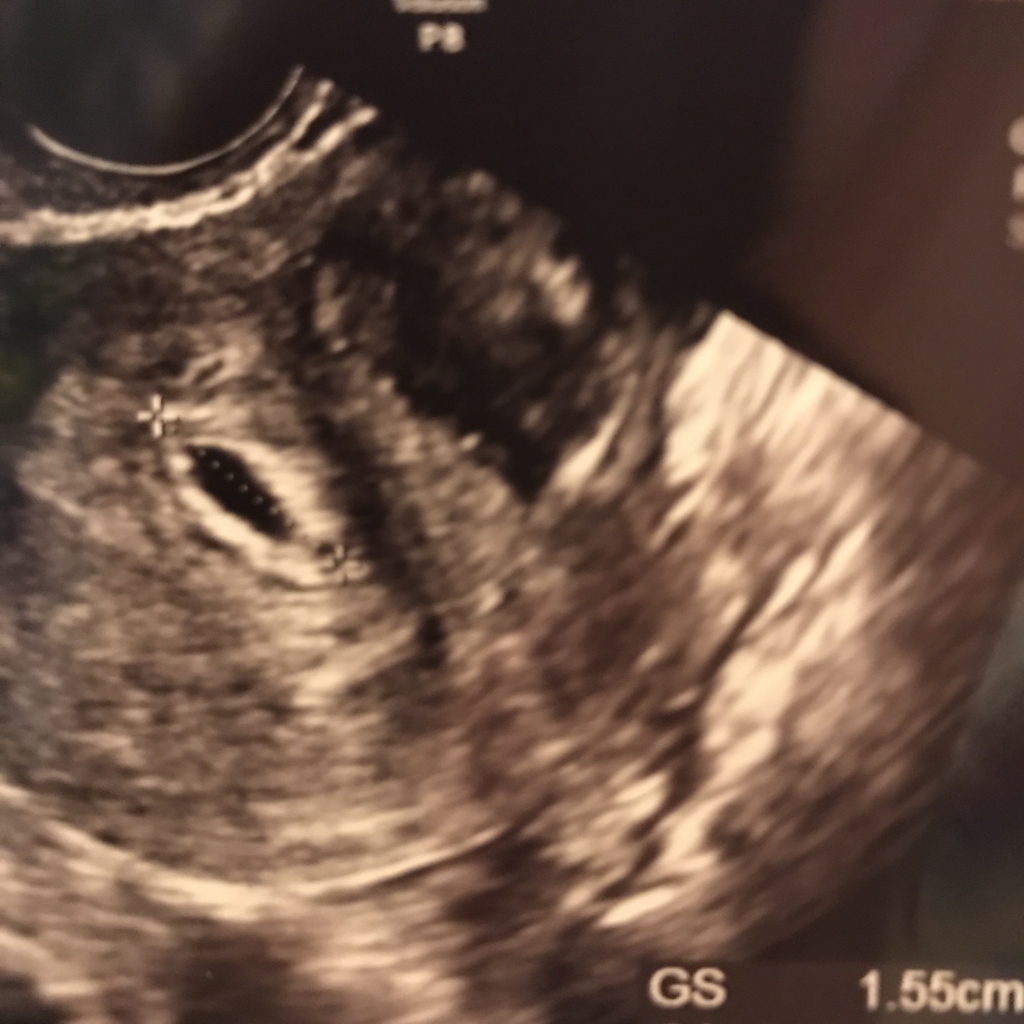

この日GS15.5mmで感動の胎嚢確認!

前回は胎嚢確認にも至らず流産してしまったので、

はじめて胎嚢を見た時は感動で泣きそうになってしまいました…